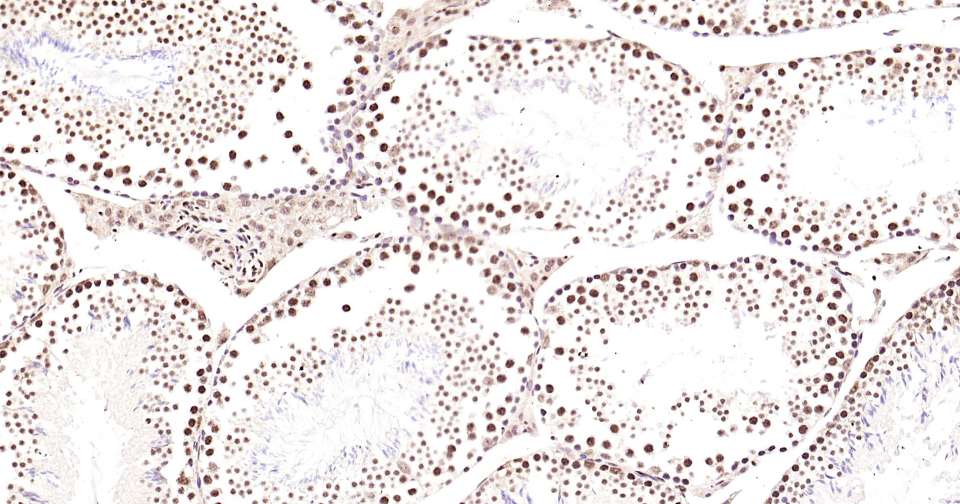

Immunohistochemical analysis of paraffin embedded mouse testis tissue slide using IHC0345M (Mouse Phospho-CREB-1 (Ser133) Kit).